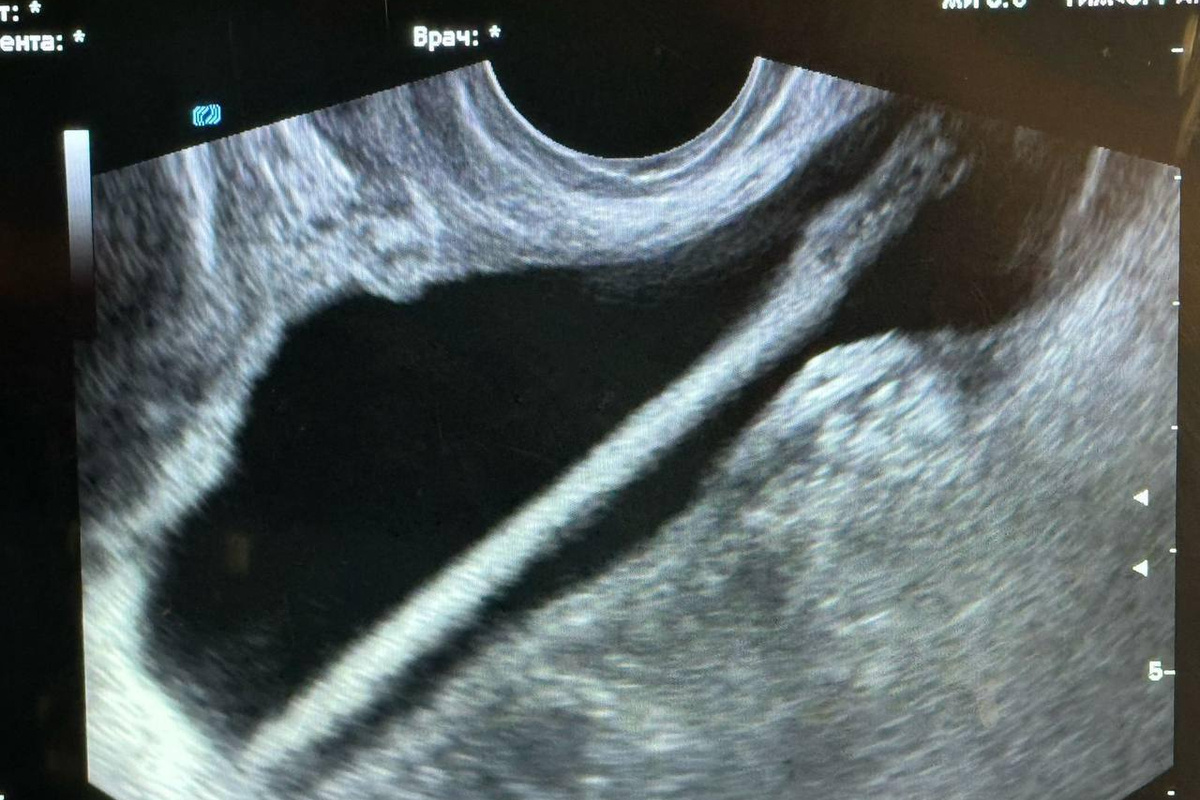

В Красногорскую больницу была доставлена 46-летняя пациентка, которая сообщила, что сама ввела себе косметический карандаш в уретру. По ее свидетельству, предмет проник в мочевой пузырь.

Заведующий отделением Петр Сысоев пояснил, что первоначально было проведено ультразвуковое исследование. Затем доктора осуществили хирургическую операцию, в ходе которой при помощи эндоскопа удалось извлечь инородный объект из мочевыделительной системы. Он добавил, что процедура прошла успешно и без осложнений.